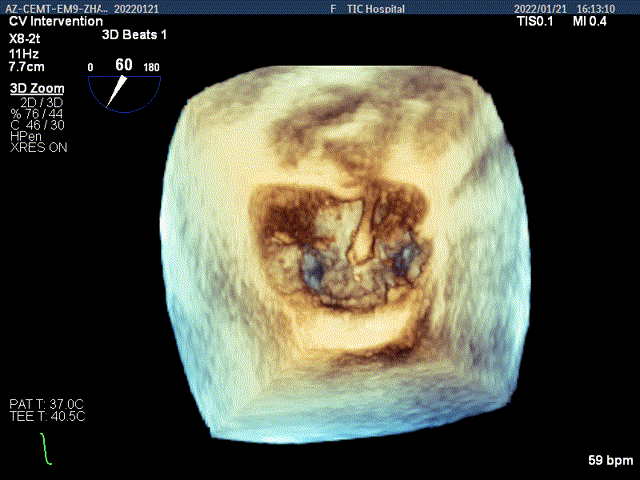

3D MV View:P2区脱垂,宽16.3mm,P3区瓣叶膨隆,与前叶对合不良

Qlab软件勾画估测瓣口面积约:4.42cm²

TEE Bicom view:二尖瓣后叶P2区脱垂,宽16.3mm